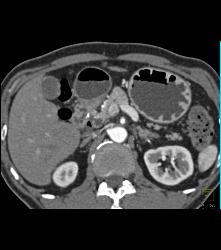

Antral Carcinoma